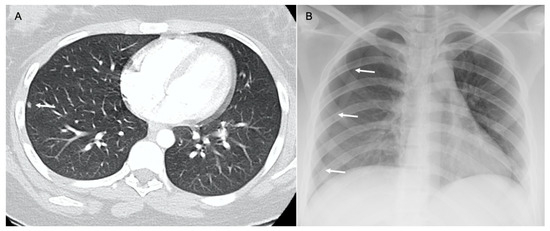

6. Chest Wall